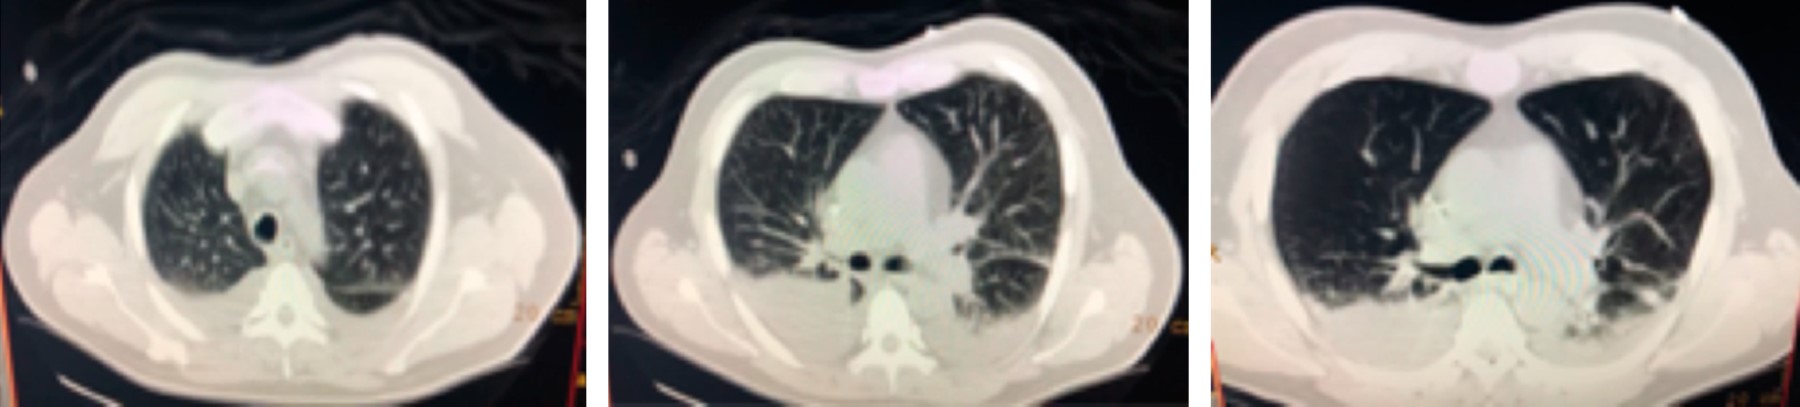

El paciente presenta mejoría relativa, se decide su extubación, un día posterior a esto persiste con deterioro clínico, se amplia cobertura de antimicrobianos para Staphylococcus aureus meticilino-resistente, se solicita nueva tomografía de tórax para control, en la cual persisten las zonas de consolidación en lóbulos inferiores, agregándose derrame pleural bilateral, el resto del estudio sin cambios significativos respecto al previo (Figura 3).

Seis días posteriores se reporta cultivo de secreción positivo para Trichosporon asahii, cambiando caspofungina por voriconazol, logrando su egreso de la UCI. Un día posterior el paciente presenta mejoría clínica, manteniendo una evolución favorable el resto de su estancia hospitalaria en tratamiento con voriconazol. Se realiza nueva tomografía de control, la cual muestra mejoría significativa de las zonas de consolidación en los lóbulos pulmonares inferiores así como del derrame pleural, el cual mostraba resolución casi total del hemitórax izquierdo y disminución del volumen del derrame pleural derecho. Por lo anterior, se decide su egreso a domicilio posterior a 22 días de estancia intrahospitalaria. Actualmente continúa con seguimiento por consulta externa con evolución favorable.

Figura 3